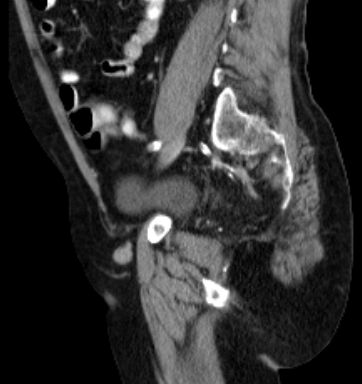

| CT | 66jähriger Mann, dass er seit einigen Wochen Blut im Stuhl gehabt habe.

Eine Koloskopie vor 6 Wochen habe einen unauffälligen Befund ergeben.

Bei der Austastung findet sich ein 5 cm großer schüsselförmiger Krater mit wulstigen Rändern.![]() | ||

Zusätzlich ein 2,5 cm großen Lymphknoten in der rechten Leiste medial der Vena femoralis. ![]() |